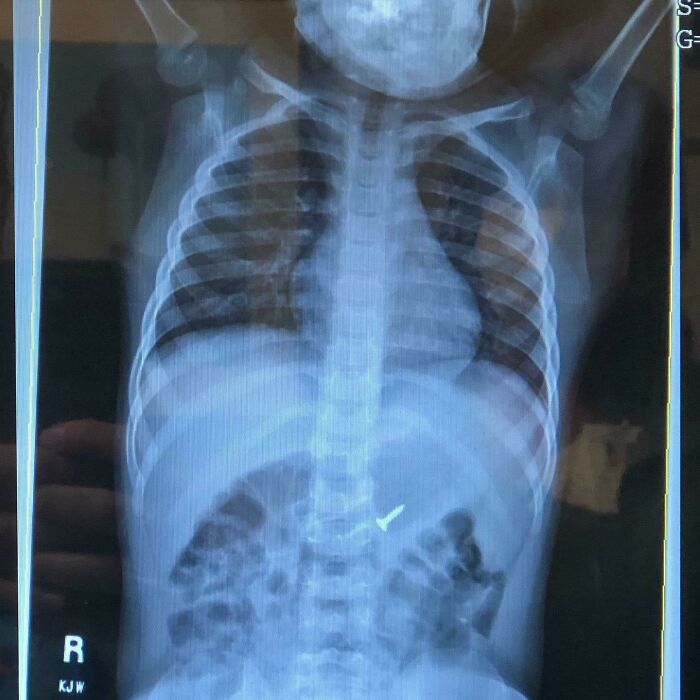

Son Decided To Swallow A Nickel And Turn $.05 Into $4400.00

And again child's play nearly bankrupts a family in the greatest country of the world.